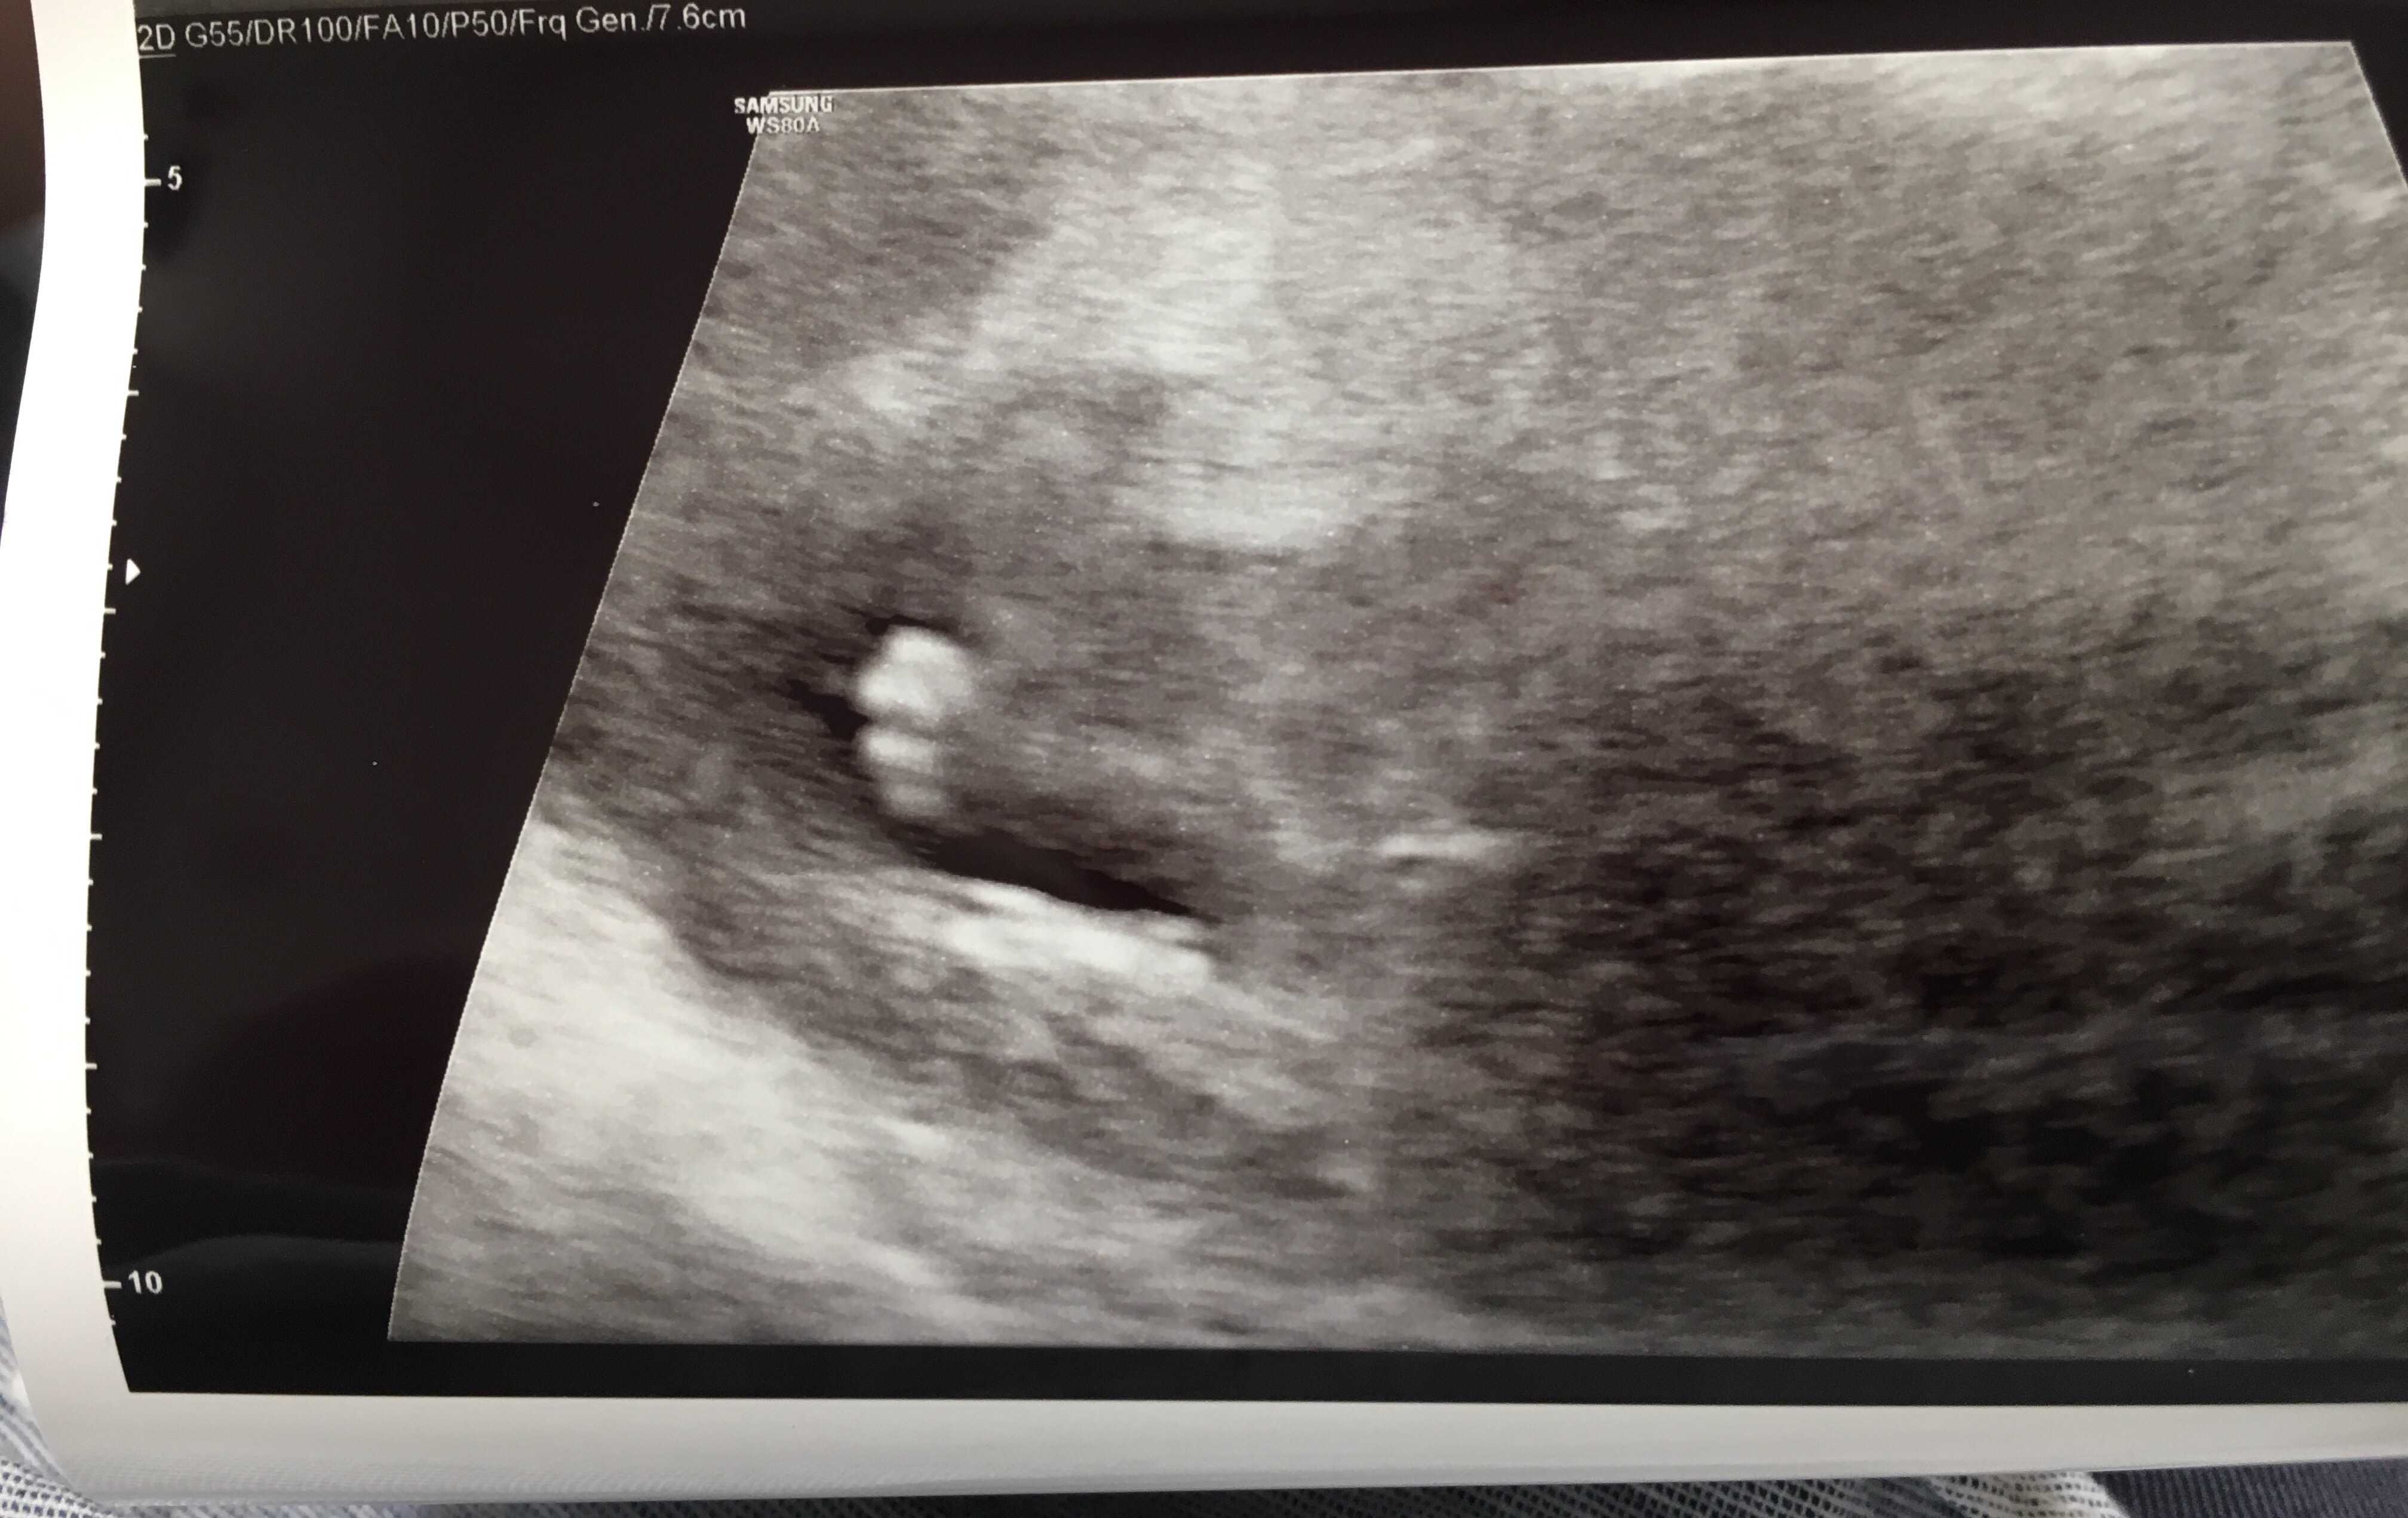

Our NT scan went well! They want the measurement to be below 3, and little miss was 1.3.

She kept dancing the whole scan. She never stopped. I’m actually already feeling her movements, and now I know why!

And, as promised…

Profile view 🙂

all the little fingers

laying with her hand above her head